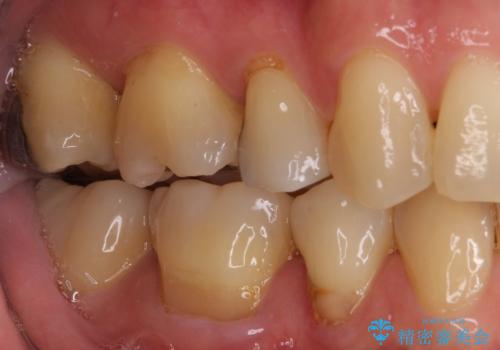

矯正治療後には、下顎臼歯の目立つ銀歯をセラミックインレーにて修復治療を行いました。

口を開けたときに金属が見えなくなり、患者様には大変満足していただきました。